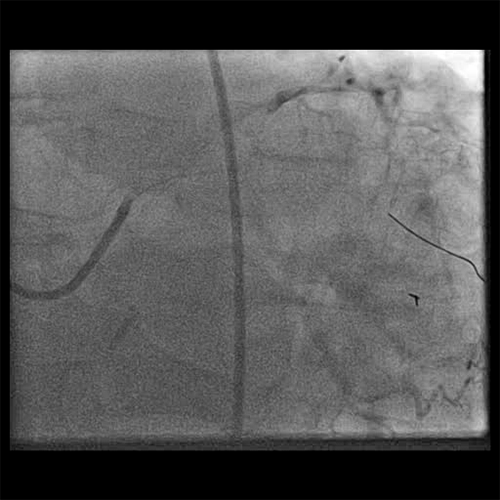

• The obtuse marginal was treated with manual aspiration thrombectomy utilizing the FETCH2 Aspiration Catheter

• A moderate amount of red thrombus was removed (Cine 3: FETCH2)

• Post FETCH2, the thrombus grade was 2